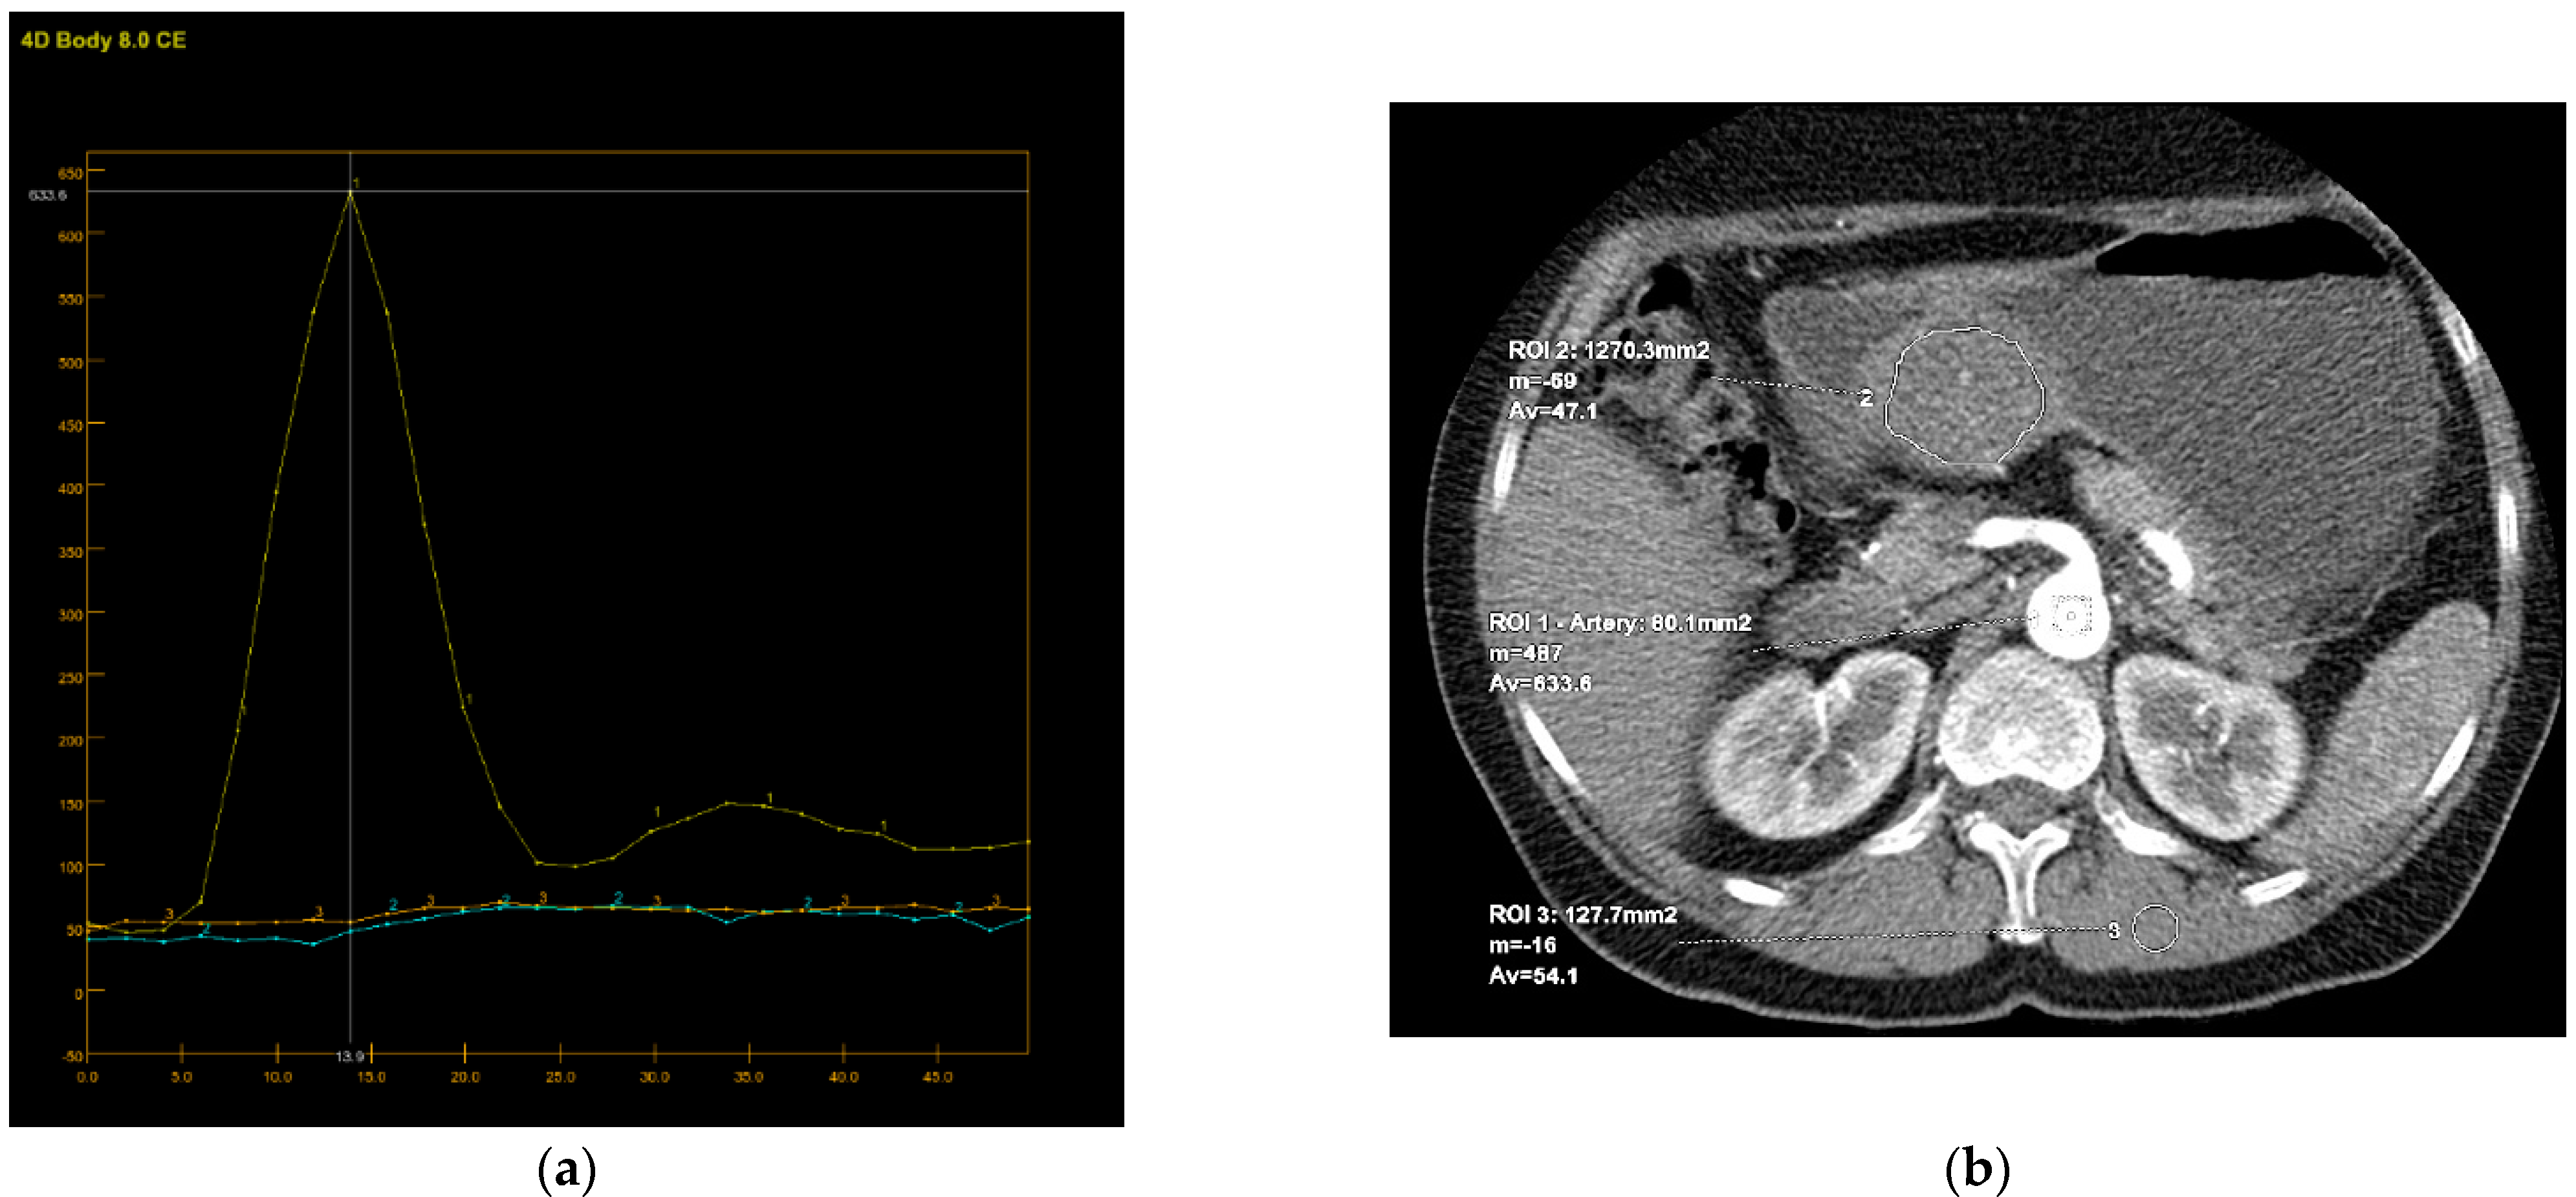

Perfusion CT data were analyzed by calculating perfusion according to the deconvolution method. The arterial input function was obtained from a 4–6 mm² circular region of interest (ROI) that was placed in the abdominal aorta. The arterial time-attenuation curve was derived automatically, and parametric colored maps were displayed for each of the four consecutive series of perfusion CT (Figure 4a). One radiologist placed a circular ROI as large as possible within the solid tumor region as well as in the nearby paravertebral skeletal muscles, taking care to avoid large vessels, at the reference and parametric images on each of the four consecutive slices (Figure 4b).

It is known that CT perfusion parameters may correlate with tumor risk. It was shown that poorly differentiated tumors have higher values of BF, BV and PS and shorter MTT than less aggressive tumors of the same type [13,25,26,27]. There are no available studies that have investigated the significance of CT perfusion in the preoperative prediction of the metastatic potential of gastric GISTs. Our results also show a tendency for higher values of perfusion parameters in highly aggressive gastric GISTs, as well as shorter MTT. However, there was no statistically significant difference except for PS and TTP. The velocity of inflow to the tumor microvasculature and capillary permeability proved to be the most reliable perfusion parameters for predicting the HR tumor with statistically significantly higher values in the group of HR GISTs, which was also confirmed by other perfusion studies on the different types of malignant tumors [26]. The TTP, indicating the time interval from the beginning of contrast administration to the peak attenuation of the tumor tissue, although a semi quantitative perfusion parameter showed a statistical significance in discriminating the HR from LR GISTs, which was proved by the univariate regression analysis. This result seems significant because there is no need for the commercial CT perfusion software to assess the TTP. The values of this perfusion parameter are available by simply reading from the time-attenuation curve of applied ROI in the CT perfusion series (Figure 4a, b), without complex calculations those are necessary for obtaining the other CT perfusion parameter values.

Figure 4. An 8-mm reconstructed image from the low-dose CT perfusion series of a 57-years old female patient with gastric GIST. Time-density curve on computed tomography perfusion (a). The arterial (yellow), tumor (blue), and muscle (orange), time-attenuation curves of the corresponding CT perfusion section. A freehand ROI (this tool measures area in square milimeters) in the region of tumor and round ROIs in the aorta and paravertebral muscle (b).